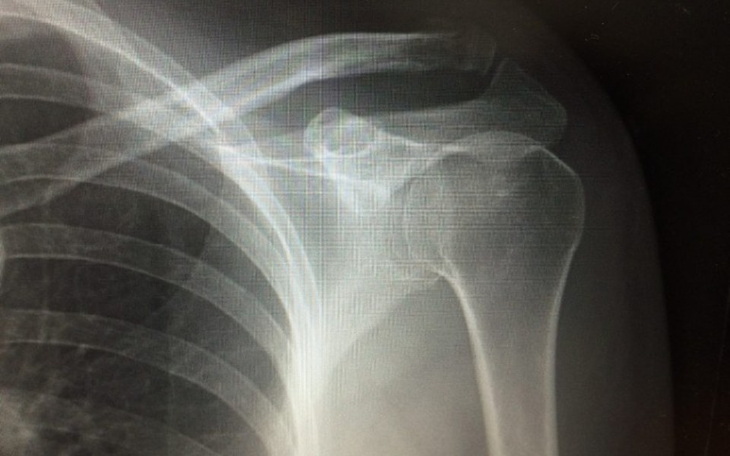

Witam wszystkich zwracam sie do osób dobrego serca chciałbym pomoc mojej cioci ktora w wypadku 14grudnia doznała złamania obojczyka jesli jest tu jakas osoba ktora moze pomoc prosze nawet 1zł dzieki